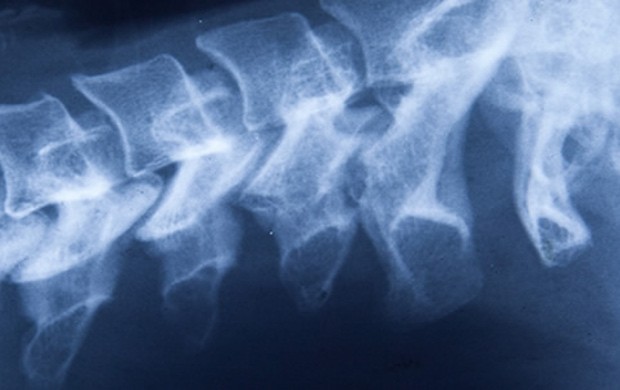

All of these can be viewed with the eye, more accurately assessed with physical therapy measuring tools or, where required, assessed where necessary by medical imaging.

In certain cases, where we hold certain postures for years, the small bones of the back—the facet joints—can in fact remodel themselves to accommodate to changes in where load is being placed through the body. Once adapted, these changes cannot be undone but may be supported by strength training to improve function at that area.